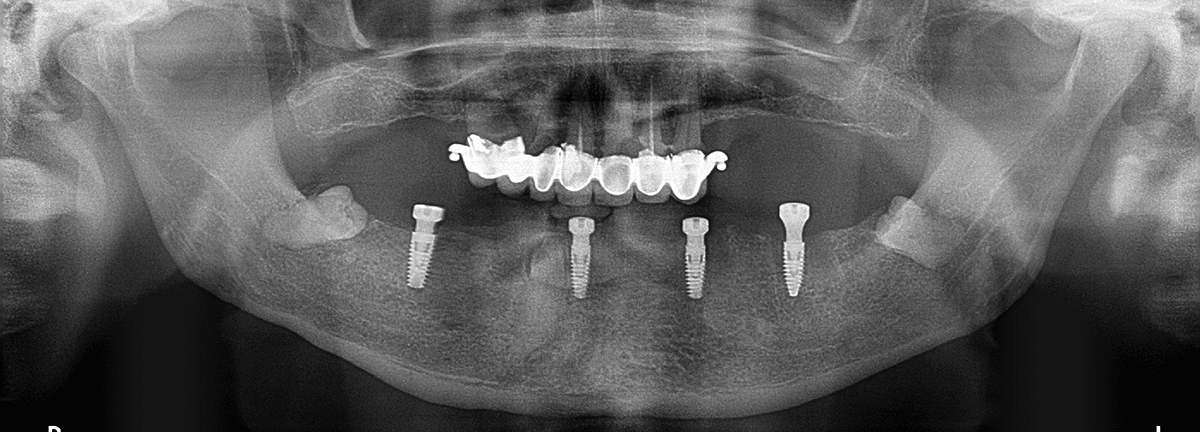

Implant to niewielka śruba wykonana najczęściej z tytanu, która zastępuje naturalny korzeń zęba. Umieszczana jest w kości szczęki lub żuchwy, a po okresie gojenia stanowi stabilną podstawę dla korony protetycznej, mostu lub większej odbudowy.

Implanty w Poznaniu są rekomendowane w przypadku pojedynczych braków zębowych, większych luk w uzębieniu, a także przy całkowitym bezzębiu.

Leczenie rozpoczyna się od konsultacji oraz szczegółowej diagnostyki obrazowej. W Praktyka Dentystyczna w Poznaniu plan leczenia oparty jest na dokładnej analizie ilości i jakości kości oraz warunków zgryzowych pacjenta.

Następnie wykonywany jest zabieg wszczepienia implantu, który odbywa się w znieczuleniu miejscowym.

Po implantacji następuje okres gojenia i integracji implantu z kością. Proces ten zwykle trwa kilka miesięcy.

Po pełnym wygojeniu lekarz mocuje koronę protetyczną, która jest indywidualnie dopasowana do kształtu i koloru naturalnych zębów.